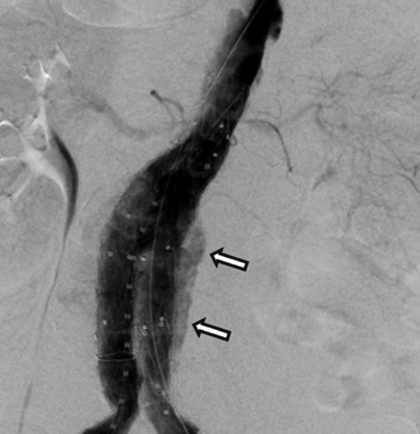

Marcelo Yáñez Lillo, Jorge Bravo López, Ismael Court Rodríguez

|